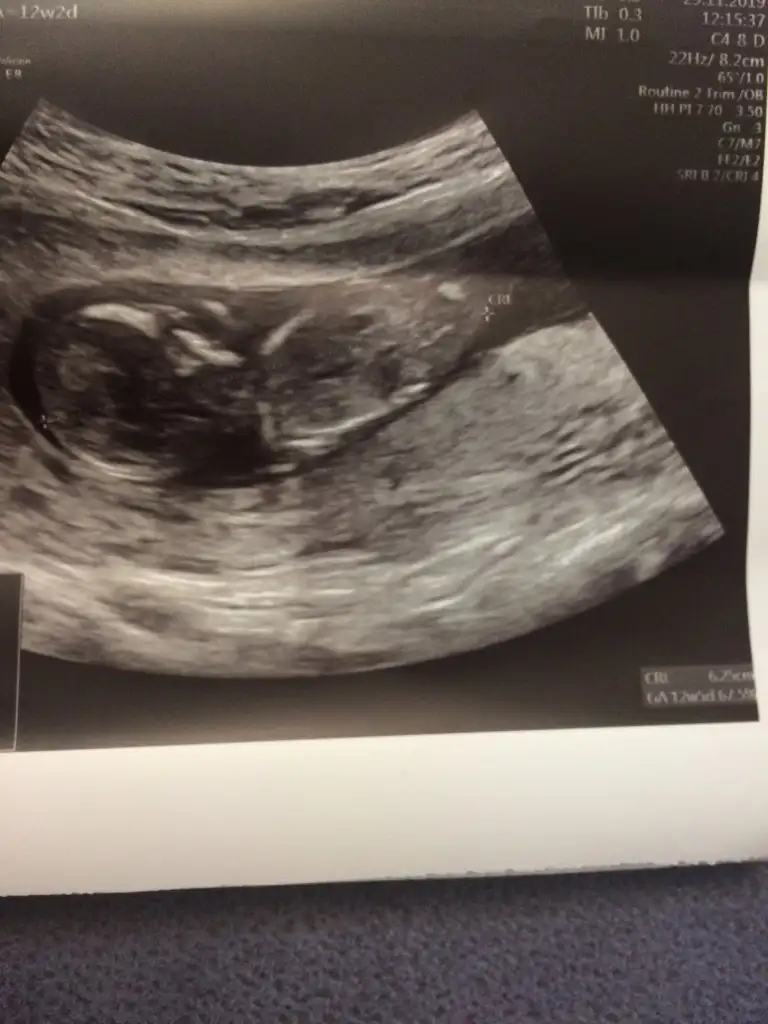

2020 Haziran Anneleri Gebelik, Ultrason, Testler, Gebelik Takibi

Normalde 12+2 yim usg de 12+5 çıktı kız gibi dedi dr kesin de konuşmadı ama plesenta serviksi kapatmış kanama olabilir dedi 😔

• 29CF45A6-A10B-46F8-B2F2-A5E5EB0C7415.webp

27,3 KB · Görüntüleme: 45